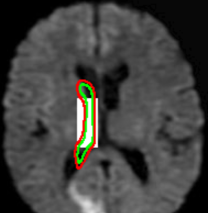

Figure 14: Segmentation of left lateral ventricle: (a) Initialization with a template (b) converged contour. Image source: Intermountain Medical Imaging, Idaho.

In Figure 13, we show the results for segmentation of endocardium in B-mode ultrasound images, an imaging modality where shape prior information is popularly[40, 41] used to counter the problem of broken/diffuse boundaries between the region of interest and its background. In Figure 14, we show an example where the template based formulation is able to overcome partial loss of signal due to occlusion and still segment the object reliably. We observe that, by incorporating prior knowledge of the shape, we can segment images with partial loss of structure and broken boundaries.

We next develop templates for objects with hole(s) in their structure. These templates are called ring templates. Figures 15 and 16 show examples of ring templates. The area enclosed between the red contours act as region 1subscript1\Re_{1} and the area between the green contours is region 0subscript0\Re_{0}. Figure 17 shows the construction of the ring contours. The two seemingly unconnected contours are actually one connected contour. Hence, partial derivative calculations in equation (26) are still valid.

In Figure 15, the ring template has been used for segmenting the left ventricular (LV) wall of heart in cardiac MR images. Another example is shown in Figure 16. The template used in both examples has a greater thickness in the inner ring-shaped annular region than the outer annular region. This was done to facilitate obtaining the desired object’s structural information by means of the contrast (for example, between the endocardium and the LV wall) that a good initialization can offer. Hence, while designing a template, we can incorporate prior knowledge of the object and its surroundings.